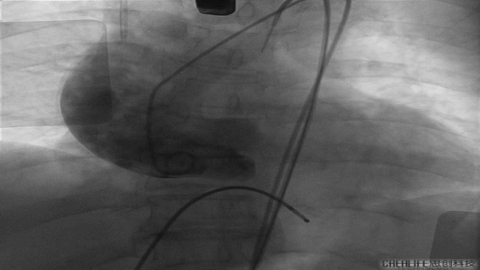

第一枪造影

跨瓣

Nmued20预扩1

Nmued20预扩2